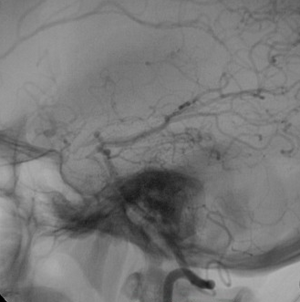

Syndrome de Moya-Moya

Il s'agit d'un syndrome radiologique caractérisé par un fin réseau anastamotique-télangiectasique se développant sur des lésions sténosantes progressivement occlusives, uni- ou bilatérales, d'artères du polygone de Willis (généralement les terminaisons des carotides internes).

Ces lésions peuvent être idiopathiques ("maladie de Moya-Moya"), héréditaires ou secondaire. Elles peuvent se compliquer d'ischémies (surtout sur les lésions sténosantes à l'origine du Moya-Moya) ou d'hémorragies (sur les télangiectasies du réseau) volontiers récidivantes.

Le syndrome est le plus fréquemment découvert chez l'enfant et l'adulte jeune.

Etiologies : idiopathique, post-radique, drépanocytose, vasculites, athérosclérose, neurofibromatose de type 1, trisomie 21,...

Une procédure de revascularisation chirurgicale (directe, indirecte, combinée) doit être systématiquement envisagée au côté du traitement d'une éventuelle pathologie causale.